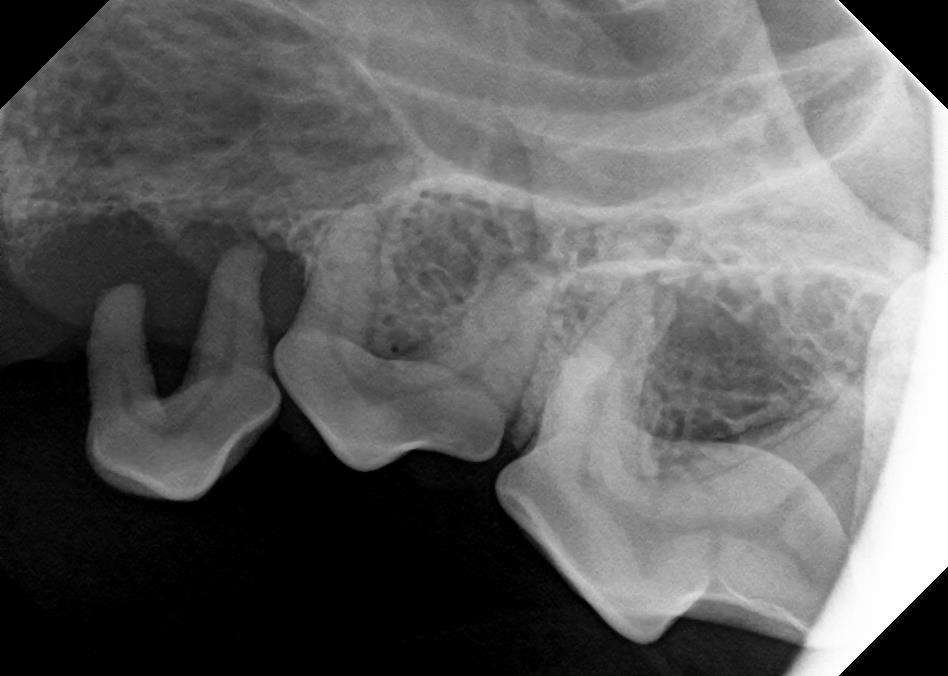

Dental X-Rays

Click on an image to learn more!